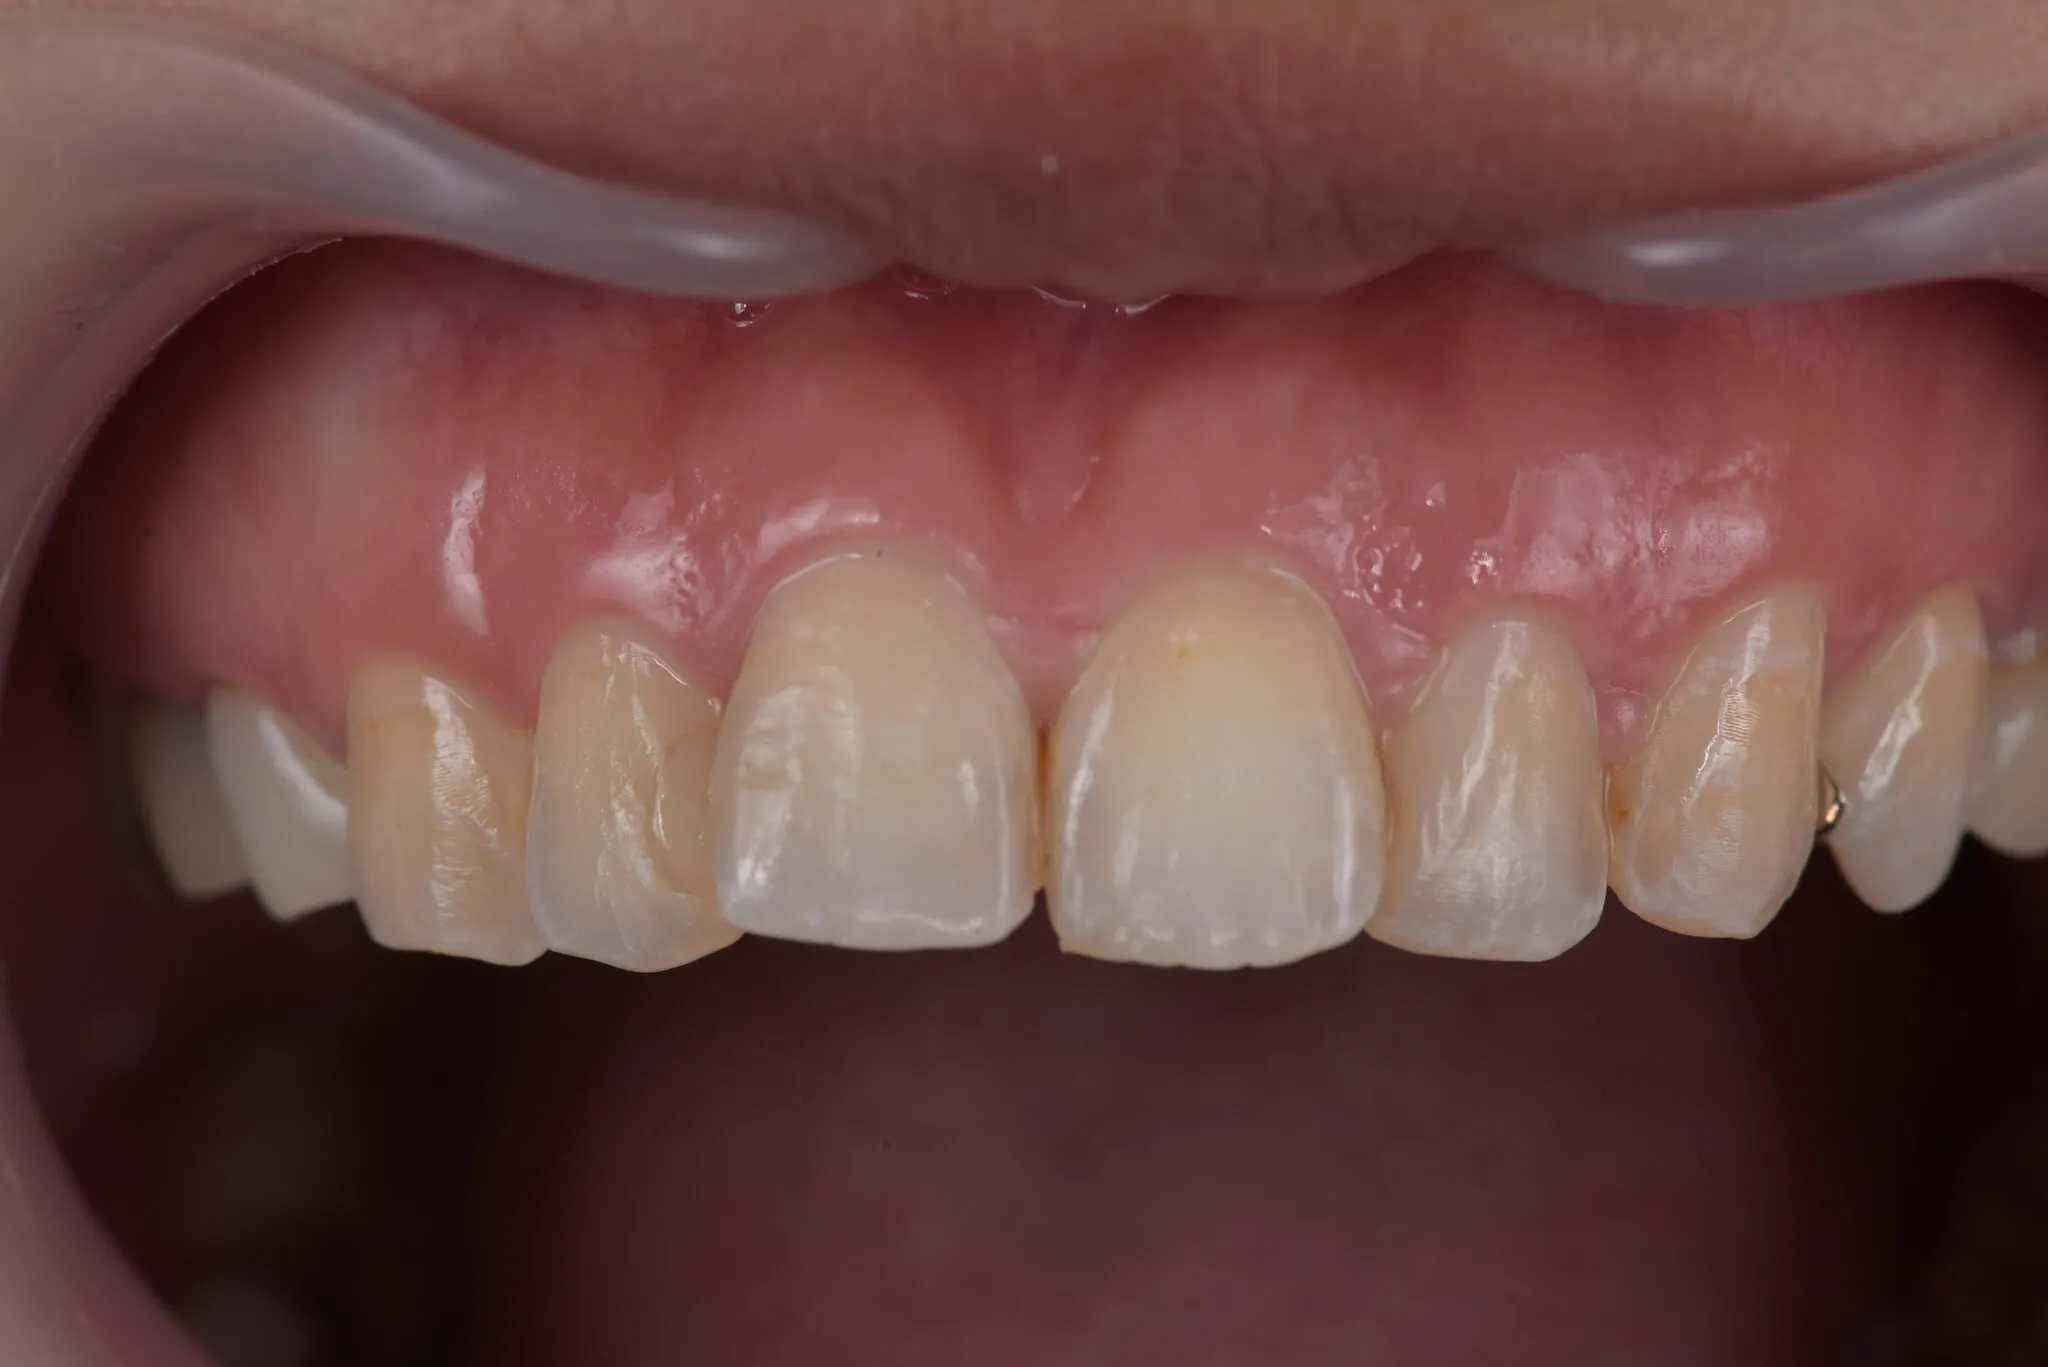

ガムブリーチ

歯の色を白くするのが通常のホワイトニングですが、歯肉が黒ずんでいるのを通常に戻すのがガムブリーチです。

歯肉はメラニン色素が付着すると黒ずんできますので、その歯肉の部分をメラニン色素除去剤で中和します。

Before

After

治療内容 | 歯肉の着色を薬液を用いて表面を一層除去し新鮮面を出す |

---|---|

治療期間 | 30分 |

治療回数 | 1回 |

リスク | 処置後数日は疼痛がある場合がある |

費用(税込) | ¥27,500 |